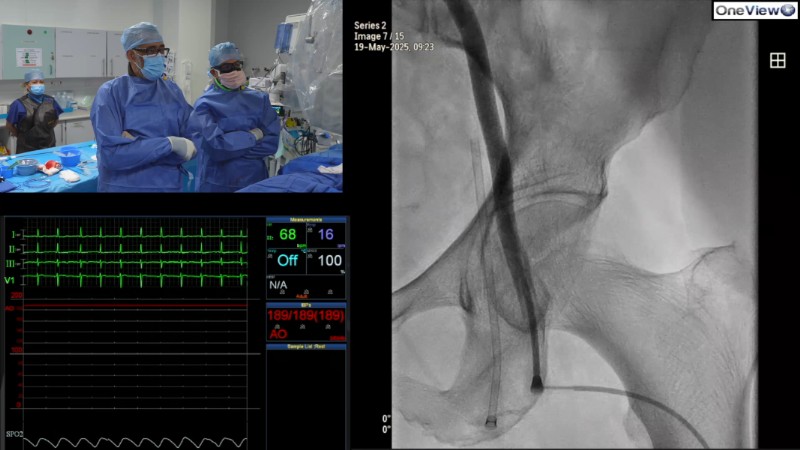

Optimising patient outcomes in self-expandable TAVI starts with a clear plan for today, and tomorrow. This EuroPCR 2025 session explores how to make each step count, from access to implantation and closure, using a real-life case of a 77-year-old woman with severe symptomatic aortic stenosis and multiple comorbidities.

- To optimise TAVI patient outcomes from initial access, optimal implantation and access closure